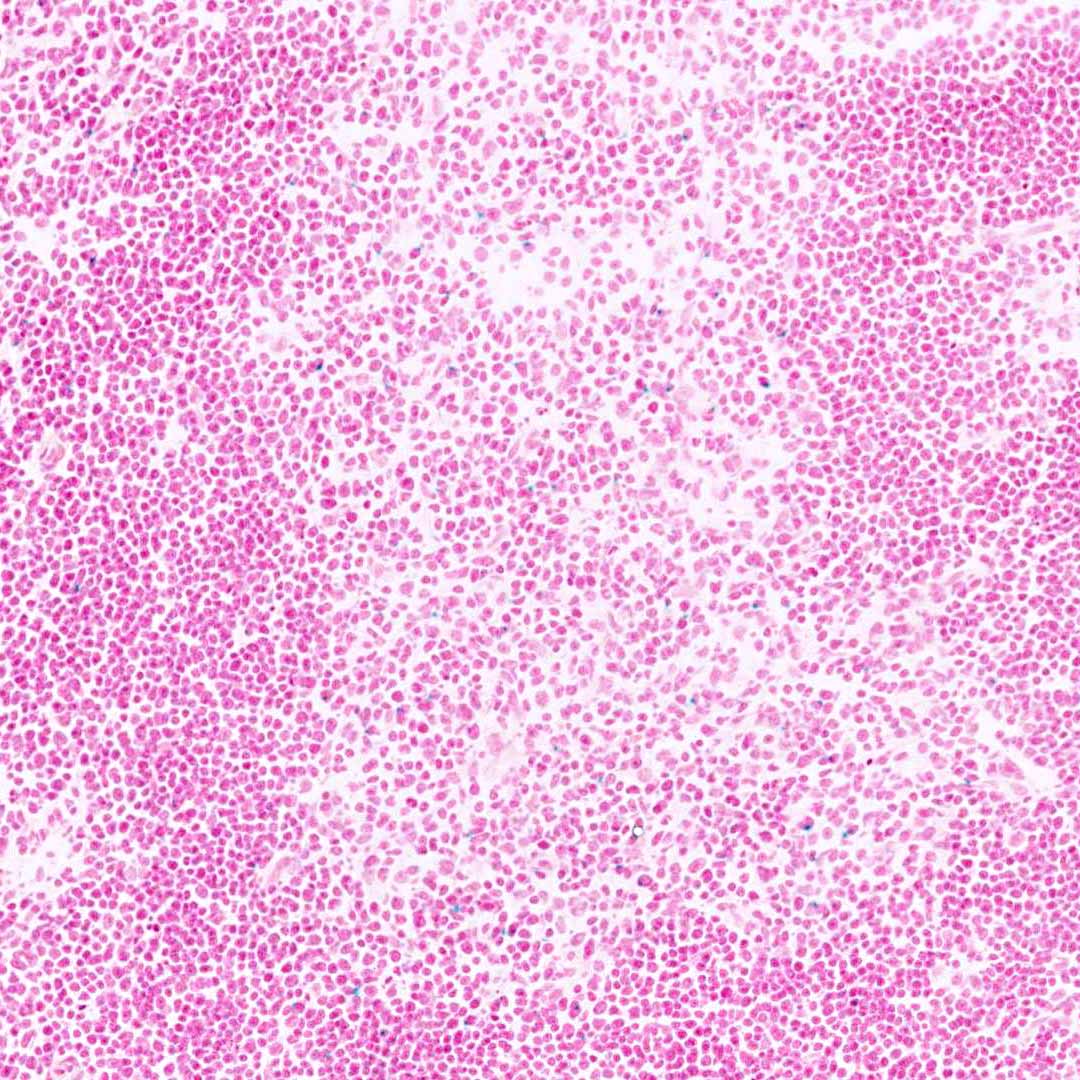

This transgene expresses the codon-improved cre recombinase (icre) open reading frame under the control of the distal Lck promoter (dLck). This transgene is expressed in T cells primarily after Tcra locus rearrangement and the cells have reached the TCRhi stage of development.

Tg(Lck-icre)3779Nik activity also observed in:

Hemolymphoid System